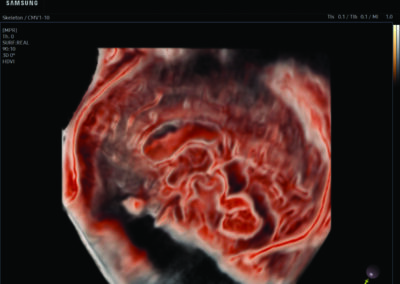

Comprehensive, advanced and expert MFM care for high-risk pregnancies